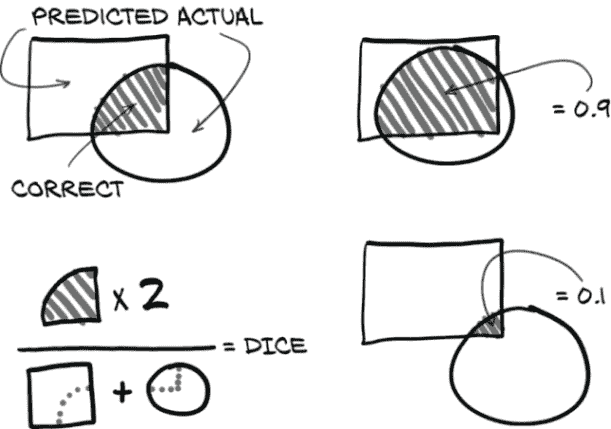

13.6.3 Dice 损失

Sørensen-Dice 系数(en.wikipedia.org/wiki/S%C3%B8rensen%E2%80%93Dice_coefficient),也称为Dice 损失,是分割任务常见的损失度量。使用 Dice 损失而不是每像素交叉熵损失的一个优点是,Dice 处理了只有整体图像的一小部分被标记为正的情况。正如我们在第十一章第 10 节中回忆的那样,当使用交叉熵损失时,不平衡的训练数据可能会有问题。这正是我们在这里的情况–大部分 CT 扫描不是结节。幸运的是,使用 Dice,这不会构成太大问题。

Sørensen-Dice 系数基于正确分割像素与预测像素和实际像素之和的比率。这些比率在图 13.15 中列出。在左侧,我们看到 Dice 分数的插图。它是两倍的联合区域(真正正例,有条纹)除以整个预测区域和整个地面实况标记区域的总和(重叠部分被计算两次)。右侧是高一致性/高 Dice 分数和低一致性/低 Dice 分数的两个典型示例。

图 13.15 组成 Dice 分数的比率

这可能听起来很熟悉;这是我们在第十二章中看到的相同比率。我们基本上将使用每像素的 F1 分数!

注意 这是一个每像素的 F1 分数,其中“总体”是一个图像的像素。由于总体完全包含在一个训练样本中,我们可以直接用它进行训练。在分类情况下,F1 分数无法在单个小批量上计算,因此我们不能直接用它进行训练。

由于我们的label_g实际上是一个布尔掩码,我们可以将其与我们的预测相乘以获得我们的真正正例。请注意,我们在这里没有将prediction_devtensor视为布尔值。使用它定义的损失将不可微分。相反,我们将真正正例的数量替换为地面实况为 1 的像素的预测值之和。这收敛到与预测值接近 1 的相同结果,但有时预测值将是在 0.4 到 0.6 范围内的不确定预测。这些未决定的值将大致对我们的梯度更新产生相同的贡献,无论它们落在 0.5 的哪一侧。利用连续预测的 Dice 系数有时被称为软 Dice。

这里有一个小小的复杂性。由于我们希望最小化损失,我们将取我们的比率并从 1 中减去。这样做将反转我们损失函数的斜率,使得在高重叠情况下,我们的损失较低;而在低重叠情况下,它较高。以下是代码中的样子。

列表 13.24 training.py:315,.diceLoss

def diceLoss(self, prediction_g, label_g, epsilon=1):

diceLabel_g = label_g.sum(dim=[1,2,3]) # ❶

dicePrediction_g = prediction_g.sum(dim=[1,2,3])

diceCorrect_g = (prediction_g * label_g).sum(dim=[1,2,3])

diceRatio_g = (2 * diceCorrect_g + epsilon) \

/ (dicePrediction_g + diceLabel_g + epsilon) # ❷

return 1 - diceRatio_g # ❸

❶ 对除批处理维度以外的所有内容求和,以获取每个批处理项的正标记、(软)正检测和(软)正确正例

❷ Dice 比率。为了避免当我们意外地既没有预测也没有标签时出现问题,我们在分子和分母上都加 1。

❸ 为了将其转化为损失,我们取 1 - Dice 比率,因此较低的损失更好。